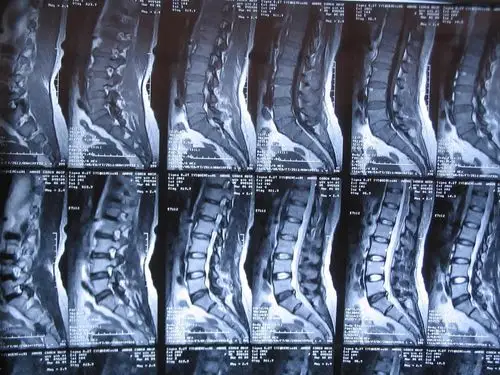

请教我读张腰椎ct片